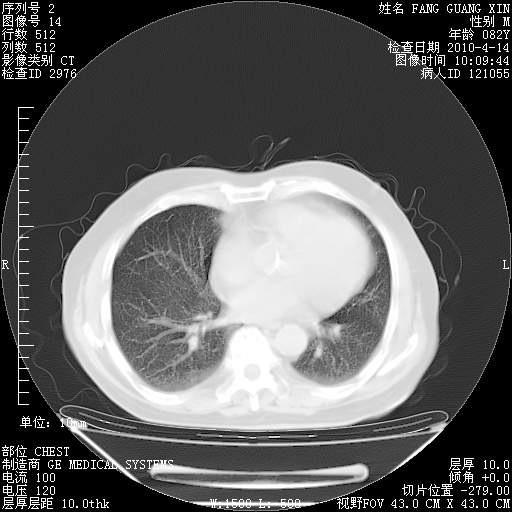

4月14日肺部CT

肺部CT平扫未见异常。

4月28日肺部CT——再次出现类似去年5月9日——透光度降低,(影像科认为)“间质性”改变。

4月28日肺部CT——再次出现类似去年5月9日——透光度降低,“间质性”改变。